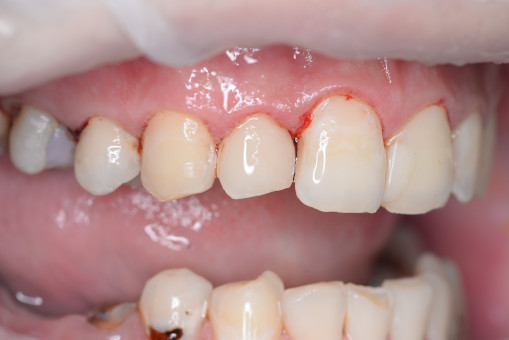

Занимаясь вопросами гигиены уже более 20 лет, мы сформировали четкое сочетание персонифицированной гигиены, нутритивно поддержки и инновационных технологий, имея при этом самое современное,на сегодняшний день, оборудование. Наша технология лечения десен не стоит больших денег и доступна практически каждому! Уникальная комплексная иммуномодулирующая методика лечения десны, в основе которой используется гидротерапия высоким давлением, является нашей гордостью и эксклюзивно внедрена в повседневную стоматологическую практику врачей–пародонтологов сети стоматологических клиник Руссдент.

Философией успеха считаем комплексный подход в лечении, состоящий не только из профессиональных манипуляций врача, но и вовлеченности в процесс пациента, от которого тоже зависит результат стойкой ремиссии. Мы вместе восстанавливаем иммунитет! Иммунитет полости рта. Восстанавливая здоровье десны и «освобождая» пациента от необходимости регулярной профессиональной чистки зубов!

А прежде, чем вы посмотрите фотографии «до» и «после» лечения слизистой оболочки полости рта, проведенных в нашей клинике, хочу поблагодарить большое количество наших пациентов, которые поверили, прониклись нашей концепцией, и мы вместе, именно вместе победили болезни десны, гингивит и пародонтит!

До/после лечения